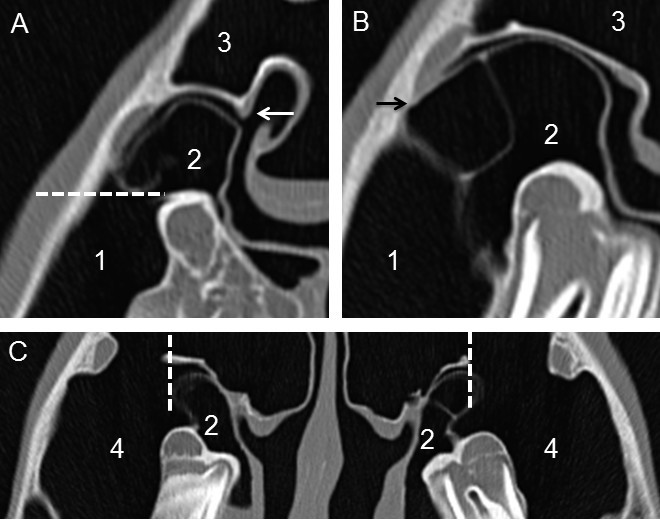

The first slice for segmentation was defined to be the most rostral one, in which the sinonasal channel is in continuous communication with the paranasal sinuses (SMR or SCV). The landmark for the medial beginning of manual segmentation in the middle meatus was a typically seen bony ‘hook’ orienting dorsally from the lamella of the dorsal conchal sinus (Figure 2A). The lateral ending for manual segmentation of the communication ways was defined as: 1. horizontal line, drawn between the most ventral point of the spiral lamella of the ventral conchal sinus to the maxillary bone (Figure 2A), 2. limited by the fusion of the spiral lamella of the ventral concha with the maxillary bone (Figure 2B), 3. vertical line beginning ventrally at the maxillary septum, ending dorsally at the lamella which forms the floor of the dorsal conchal sinus and the frontomaxillary aperture (Figure 2C).

Illustration of limits for segmentation of the sinonasal channel in transversal CT-slices. In a CT-slice at the level of 109 (A), the medial limitation for segmentation was a ‘hook’ protruding from the spiral lamella of the dorsal concha into the middle meatus (white arrow). The broken line shows the intrasinuidal limit for segmentation of the rostral sinonasal channel. In the CT-slice at the rostral level of 110 (B), the fusion of the spiral lamella of the ventral concha with the maxillary bone can be seen (black arrow). At the caudal level of 110/210 (C), the broken line displays the intrasinuidal limit for segmentation of the caudal sinonasal channel. Please note the differences of the ‘bulla’-like protrusion of the SCV (Bulla septi sinuum maxillarium) between left and right side. Numbered structures: (1) SMR, (2) SCV, (3) SF, (4) SMC.